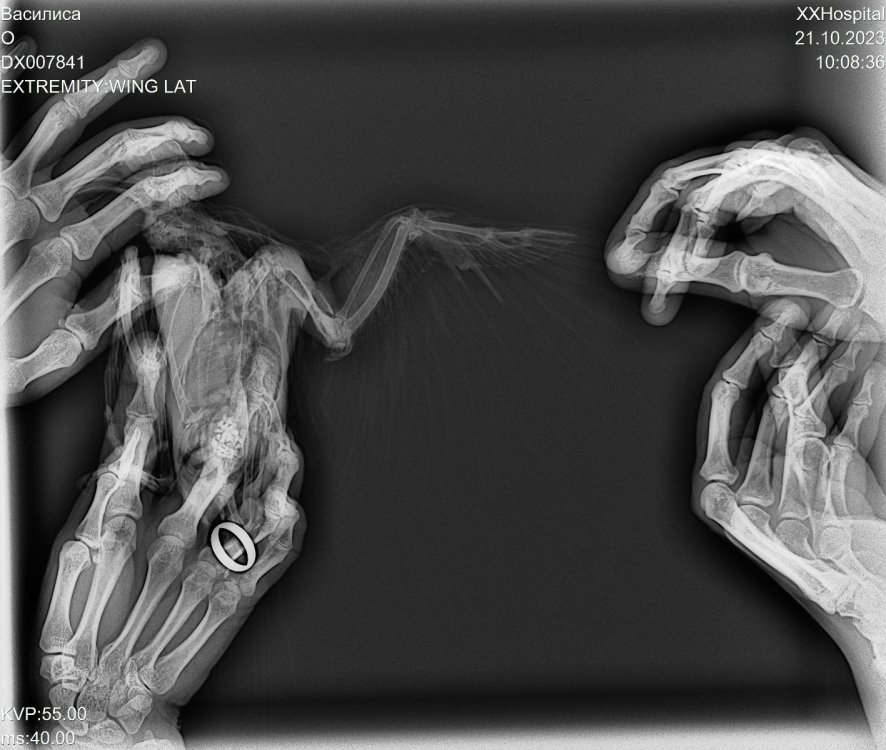

Здравствуйте. Ездили на рентген. Может кому нибудь пригодится вариант ,,упаковки,, с прищепками

Снимок

DX007841_1.jpg

20 часов назад, Patata сказал:

Доброе утро. Пригласите, пожалуйста, Доктора Зосю. Мне необходимо компетентное мнение по рентгену. Очень прошу. Спасибо.